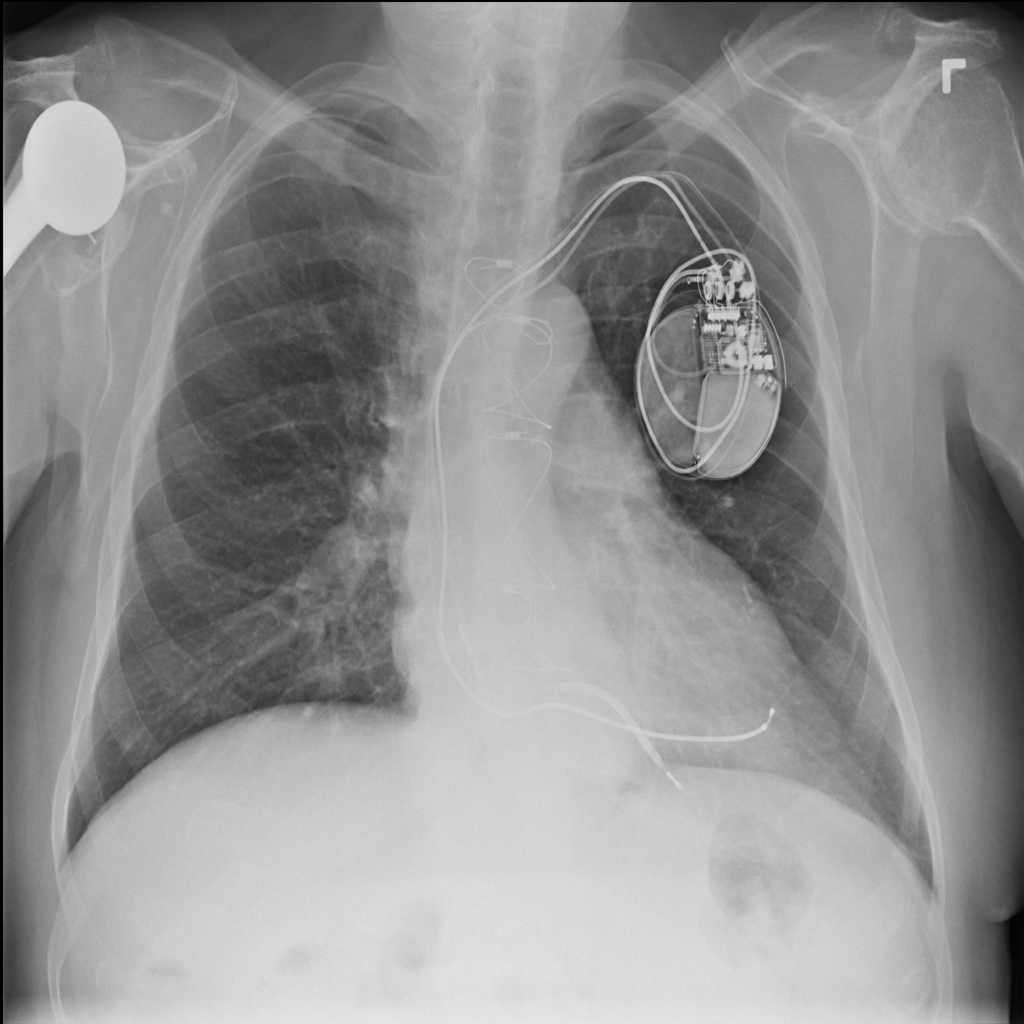

PAT-4F7E · IMG-000Hernia

PAT-4F7E · IMG-000

PA